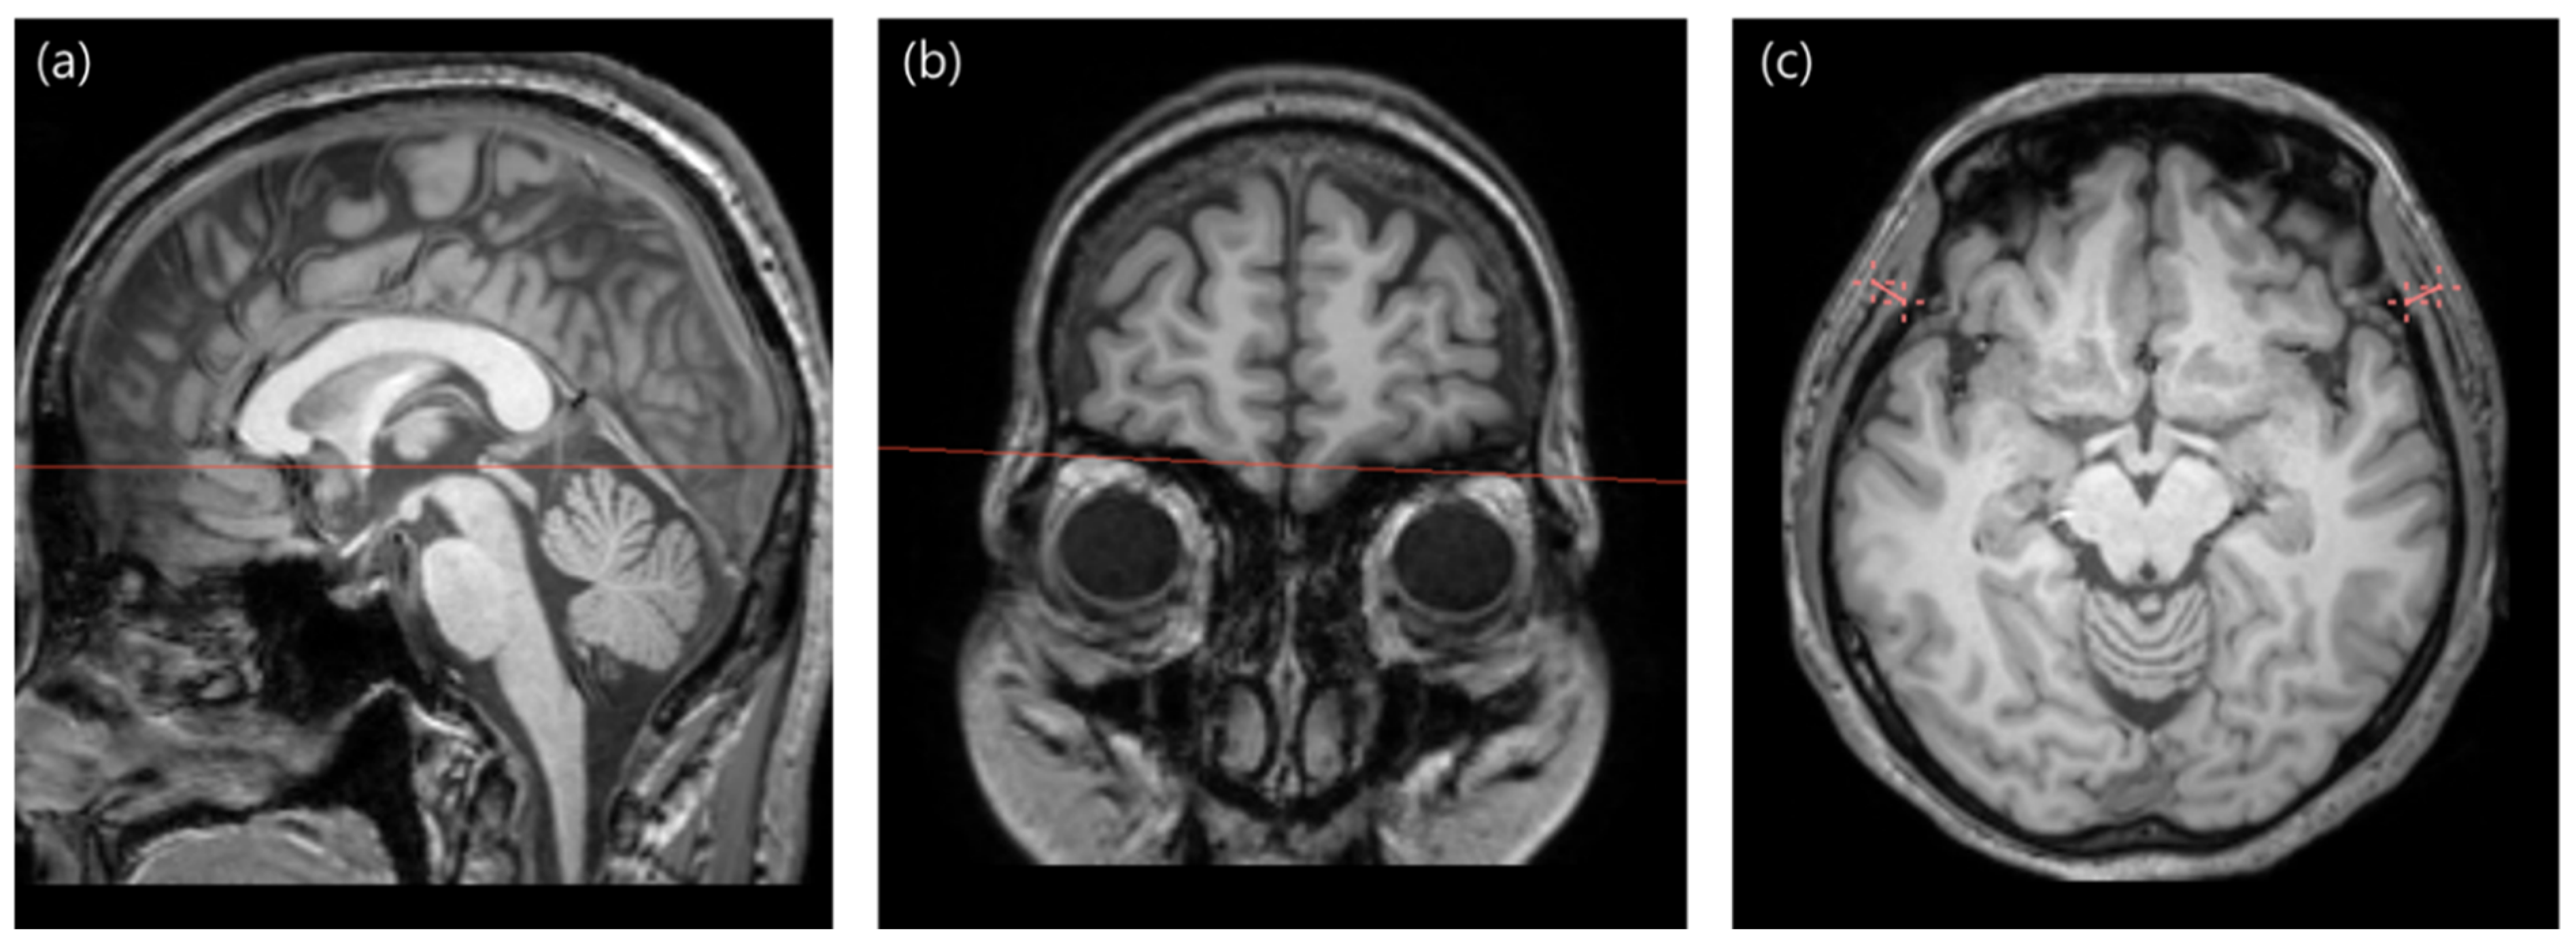

2.2. MRI Acquisition

2.3. TMT Measurement